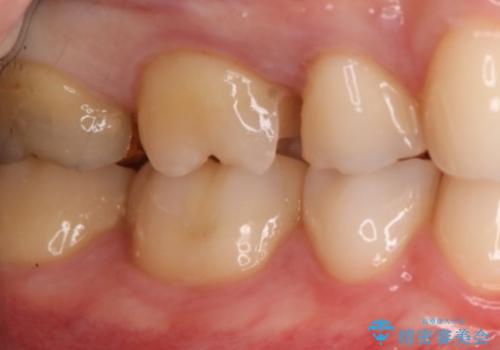

- 右上6番の銀歯のやりかえを希望し来院された患者様です。

切削量や形状からインレーでの治療を計画しました。

ご本人が金歯を希望されたため、ゴールドインレーでの治療を選択しました。

ゴールドは歯科治療に適している金属と言われ、アレルギー反応も起こしません。

奥歯の治療によく使われます。